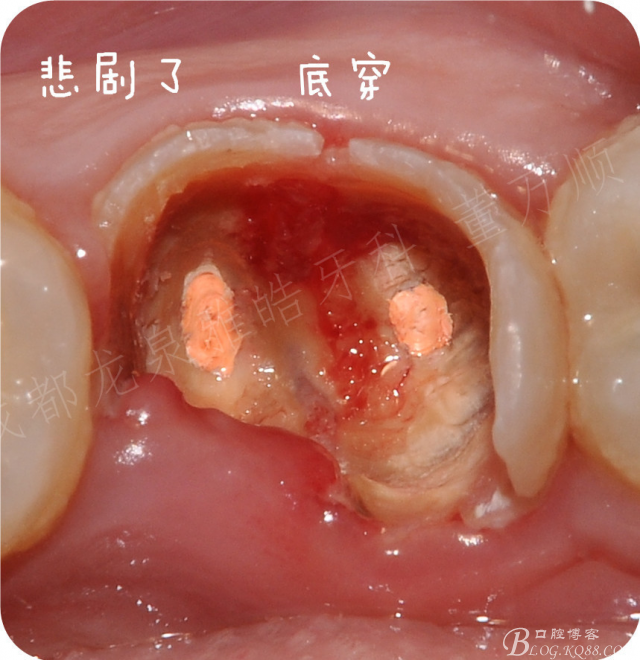

术前沟通 这个患牙保留希望实在是太渺茫了,首选建议是拔出后修复,没有任何症状的患牙 患者不愿意拔出, 想死马当活马医尝试保留一下。

那就开工吧,若有症状就只能拔除了,术前一定要沟通好,先用挖勺去除大量软垢 ,一眼望去厚厚的一层腐质

在去除颊侧根分叉那个位置的时候 突然出血了,心想大事不妙了

舌侧去除的时候,也有个穿孔,直接告知患者结果。

鉴于患者的强烈保留意愿 就用玻璃离子暂封观察 观察一段时间在考虑后期修复

一周后复查 暂时还没有发现有什么异常,只能先观察,也请各位老师给点实质性建议,后期怎么处理这颗患牙。